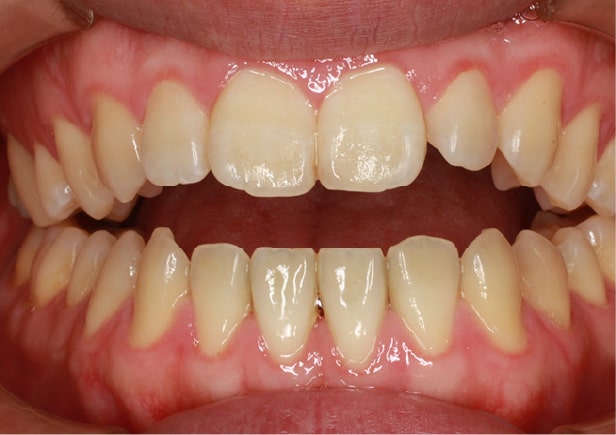

矯正bofore

矯正種類 ワイヤー矯正

症例 上下額叢生

治療期間 2021年12月〜2024年10月

性別/年代 男 13歳

治療費 748,000円

コメント

適切な時期に治療が開始できたので、歯並びだけでなく顎や顔貌も理想的に成長しました。歯磨きもしっかりできるようになりました。